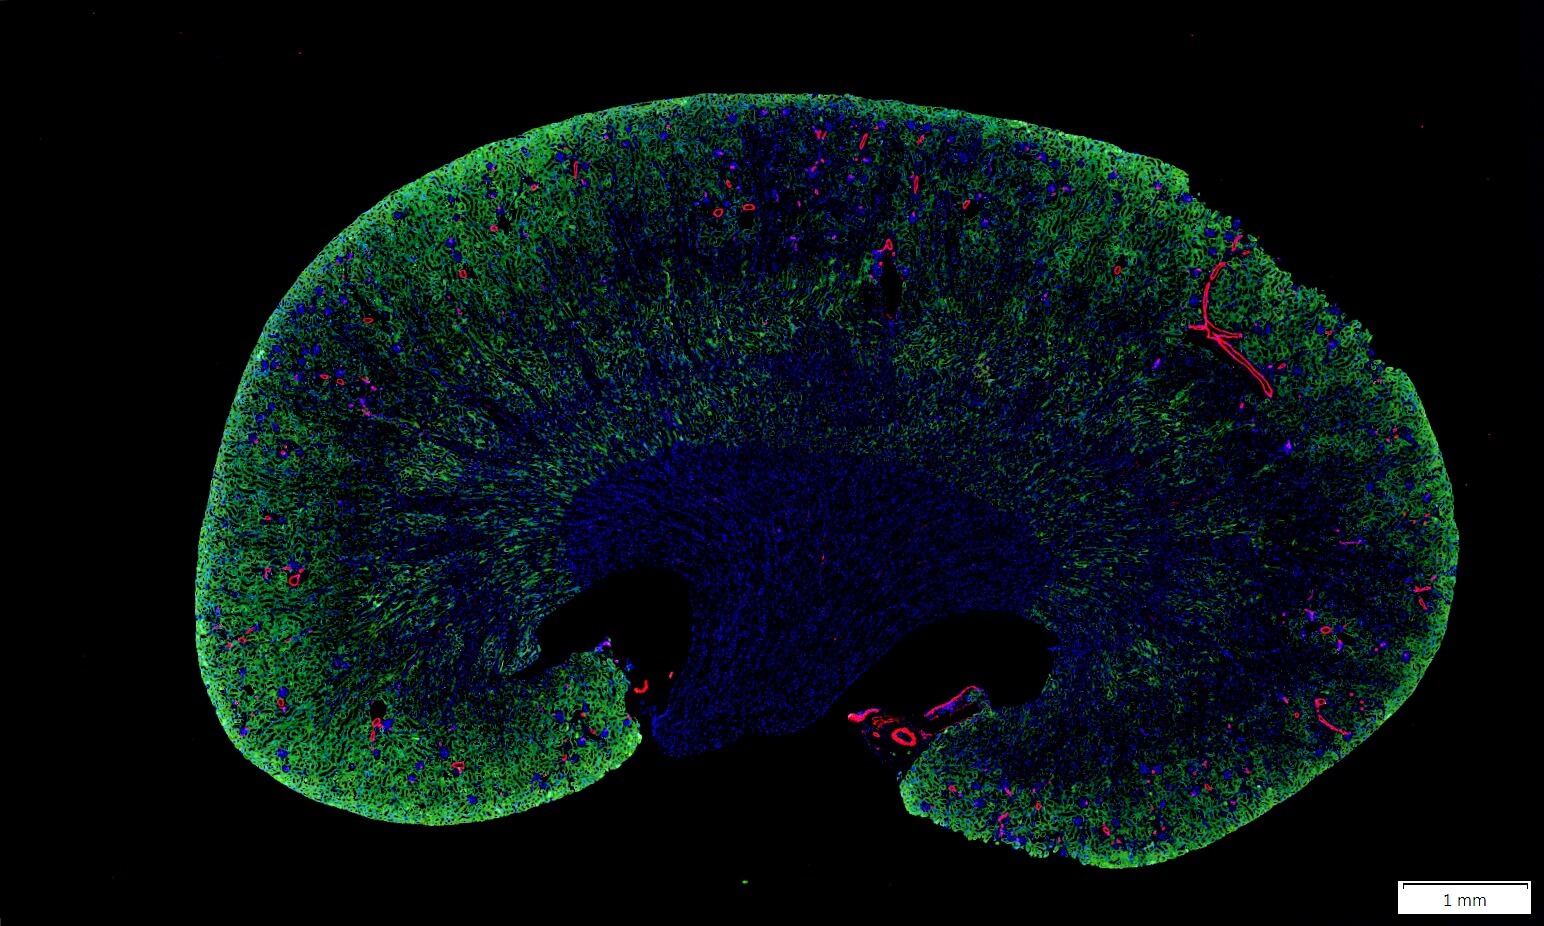

IF螢光染色